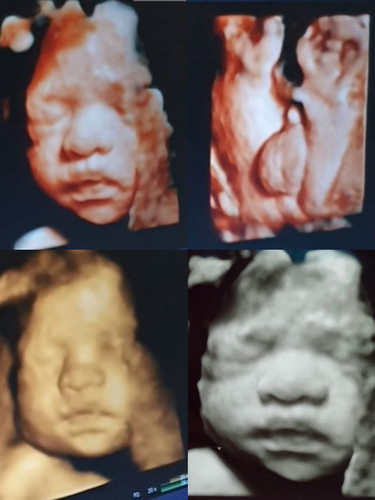

ผมหล่อไหมฮะ 55หน้ากลมดิ๊ก

รูปตอน28week

หน้าชัดมากเลยค่าสุดหล่อ